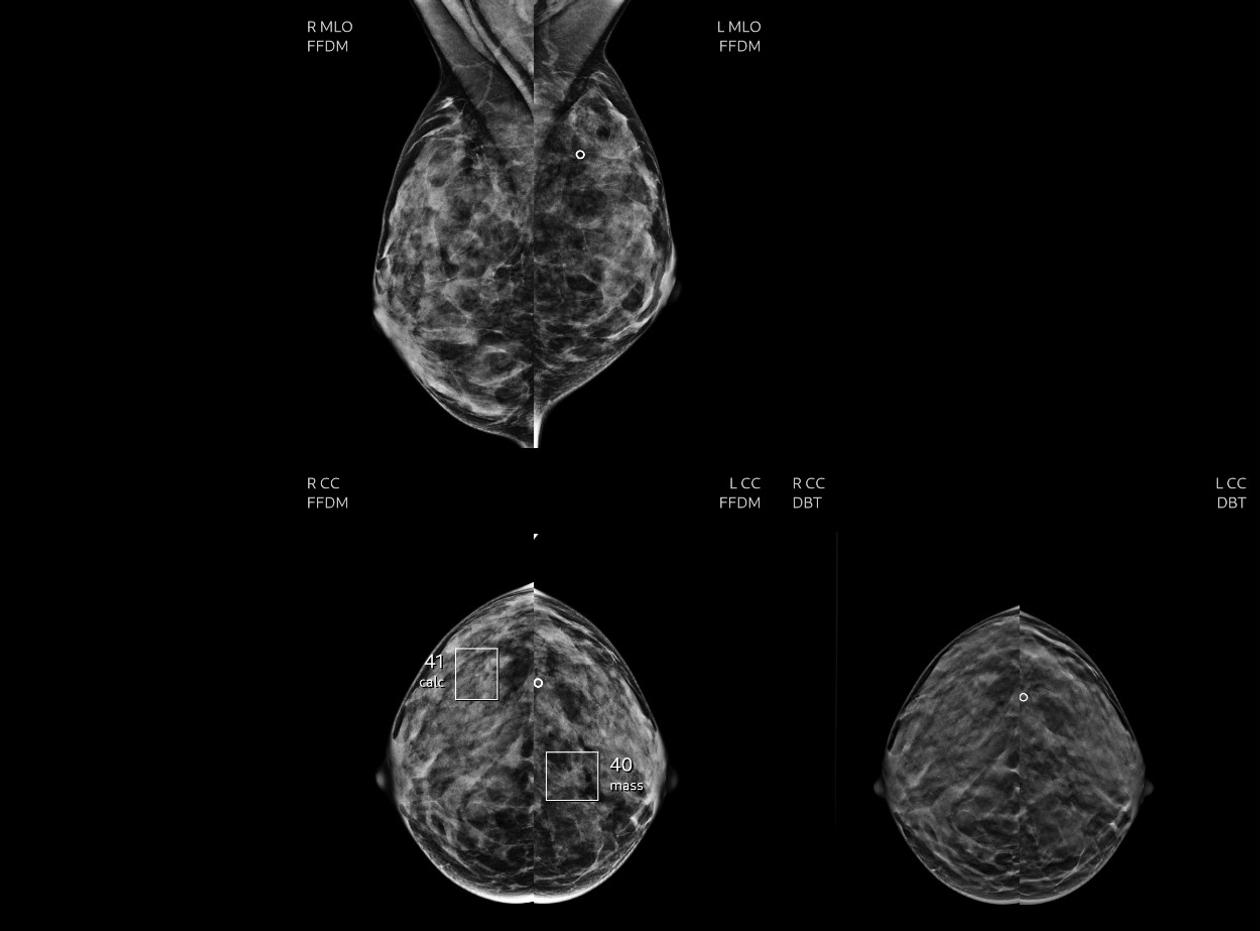

L’analyse d’images médicales (radiographies conventionnelles, mammographies…) est pour l’instant la première utilisation concrète de l’IA dans le monde, mais « une récente revue systématique a montré qu’en mammographie, par exemple, des biais méthodologiques existaient dans la plupart des études scientifiques », explique la radiologue française. Comme celle de Google Health en 2020, pourtant publiée dans la prestigieuse revue Nature, selon laquelle la machine seule dopée par l’IA faisait mieux qu’un radiologue. « Le logiciel avait été entraîné sur une population de femmes dont les seins étaient beaucoup plus porteurs de cancer qu’une population générale », explique la spécialiste.« Or, c’est bien plus simple statistiquement pour un logiciel, quand il y a beaucoup de cancers, de dire “c’est un cancer”, que quand il y en a peu. » Les performances des algorithmes peuvent aussi dépendre de la provenance géographique des images qui les ont entraînés. « Les seins des Japonaises sont très denses, alors que ceux des Européennes du Nord, appelés “seins clairs”, ont plus de graisse et sont plus faciles à lire », illustre cette experte.

A Strasbourg, au service d’imagerie de la femme de l’hôpital universitaire, l’équipe médicale utilise quotidiennement, depuis septembre 2022, une IA en seconde lecture pour les mammographies, « après l’avoir testée deux ans avec nos propres données », précise le radiologue Sébastien Molière. « Nous procédons à l’examen clinique, et prévenons les patientes qu’après la mammographie une lecture va être faite par un logiciel. Cela n’a jusqu’à présent pas soulevé de problème. » L’IA, élaborée par une start-up, alerte « plus qu’il ne faudrait et nous continuons à l’évaluer », remarque Sébastien Molière. Mais, sur quatre mois d’utilisation, à raison d’une trentaine de mammographies par jour, l’outil a permis à trois reprises d’identifier des microcalcifications, signes potentiels de précancer, qui n’avaient pas été identifiées par l’œil du praticien. Après biopsie, l’une d’elles s’est révélée cancéreuse. « L’IA va être très utile pour des professionnels sans beaucoup d’expérience, estime-t-il. Le praticien n’est jamais dans le blanc ou le noir quand il lit un cliché, alors que sa réponse doit être binaire pour le patient. C’est un outil qui peut apporter de l’assurance », précise le radiologue.